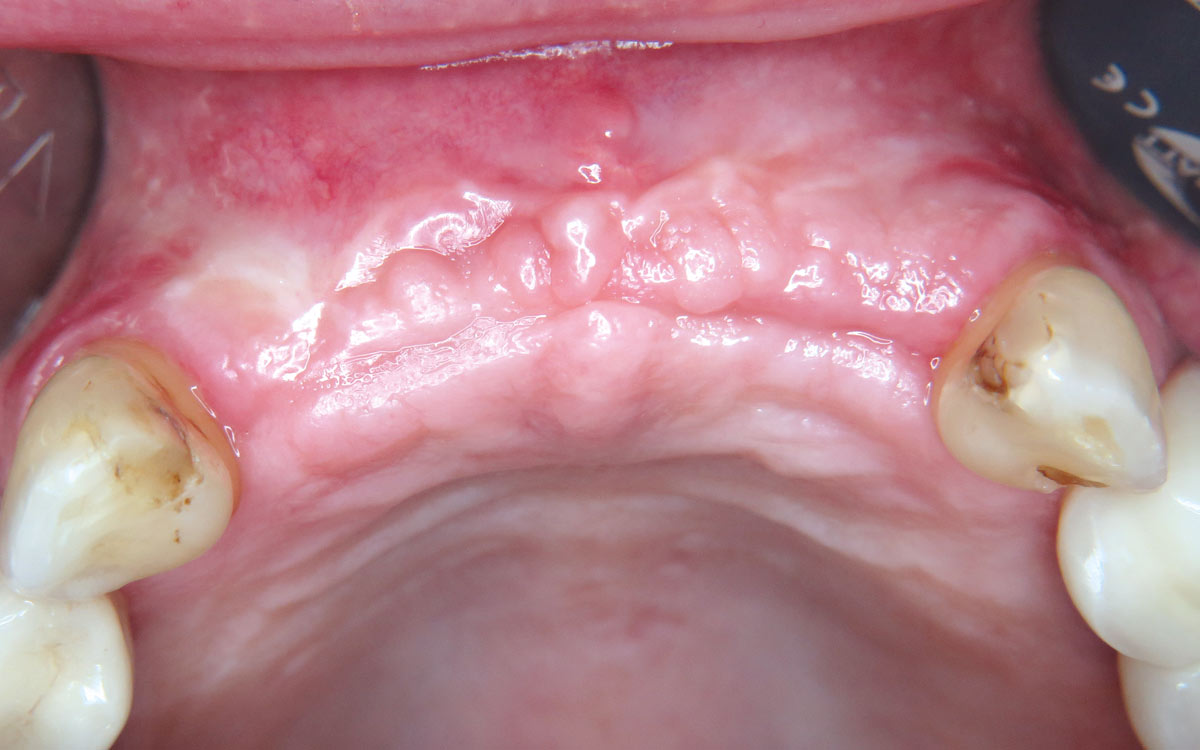

01 / 22 - Initial clinical situation – missing bonein regio 11, 12, 21, 22 and scarred soft tissue

Three-dimensional augmentation with maxgraft® cortico - M.Sc. E. Kapogianni